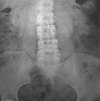

Урография образца показана в случаях подозрения на мочекаменную болезнь и в качестве первичного обследования у пациентов с нефрологической коликой и другими нефрологическими нарушениями. Рентгенограмма, полученная во время обзора урографии, включает область от верхнего края почек до уретры. Однако обычно видны только тени почек и наполненного мочевого пузыря, а мочеточники не обнаруживаются. На фото вы можете судить о положении почек и мочевого пузыря, их форме и размерах, однородности их строения и наличии камней.

Урографическое исследование - рентгенологическое исследование, отражающее строение и топографию мочевыводящих путей. Результаты урографии записываются на рентгеновской пленке и представляют собой фронтальное изображение размером 30х40 ; Процедура представляет собой стандартное рентгенологическое обследование пациента с урологическим заболеванием. На основании рентгенологического исследования было показано пространство от верхних границ почек до начальных отделов мочеиспускательного канала. Точная интерпретация результатов урографии позволяет определить дальнейшее обследование урологического больного.

В норме топография правой почки соответствует уровню грудных XII - III поясничных позвонков; слева - грудная XI проекция - II поясничного отдела позвоночника; справа граница XII находится на уровне верхнего сегмента почки, слева она пересекает центр. Когда мочевой пузырь полон, определяется эллипсоидальная тень. Контуры почек гладкие, тени однородные. При отсутствии изменений мочеточники не видны на урограмме. Тени поясничных мышц имеют форму усеченной пирамиды с вершиной в области 12-го грудного позвонка.

При опухолях, гигантских кистах почек, гематомах почек, паранефрите контуры поясничных мышц могут быть стерты или полностью отсутствуют. При пиелонефрите или остром паранефрите наблюдается увеличение плотности почечных теней и резкости контуров. Основным диагностическим значением контрольной урографии является обнаружение дополнительных теней: инородных тел, камней, кальцинов, опухолей Чтобы дифференцировать и уточнить местоположение подозрительных образований, помимо изучения урографии, используются рентгеноконтрастные исследования.